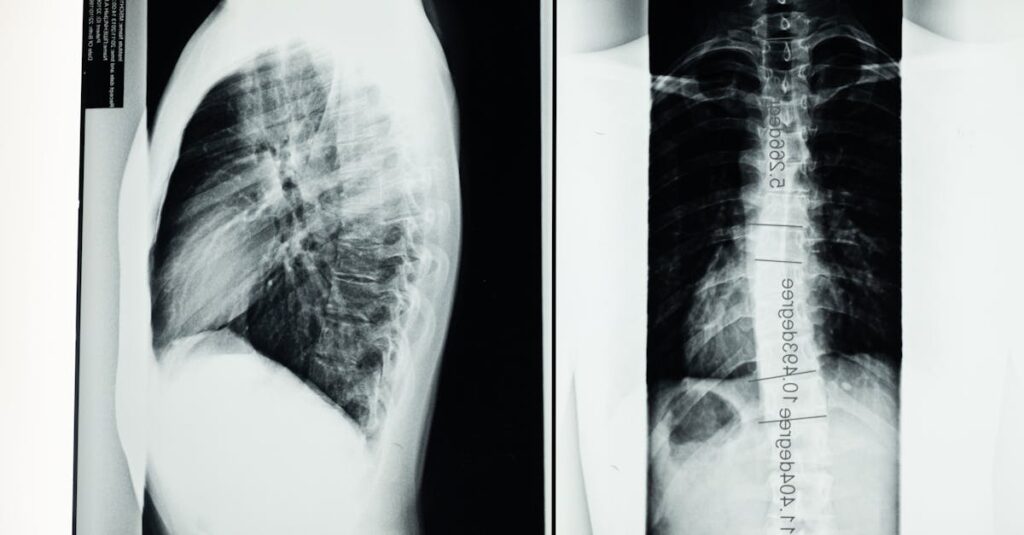

Avant d’entamer un traitement de décompression neurovertébrale, il est essentiel de consulter un professionnel de santé qualifié. Cette première étape comprend une évaluation approfondie de l’état de santé du senior, notamment l’examen de l’historique médical, des douleurs ressenties et des résultats d’imageries si nécessaires. Cela permet de déterminer l’adéquation du traitement et d’exclure d’éventuelles contre-indications.

Quels examens permettent de diagnostiquer un bombement discal?

Une IRM ou une radiographie sont les outils les plus couramment utilisés pour diagnostiquer un bombement discal.